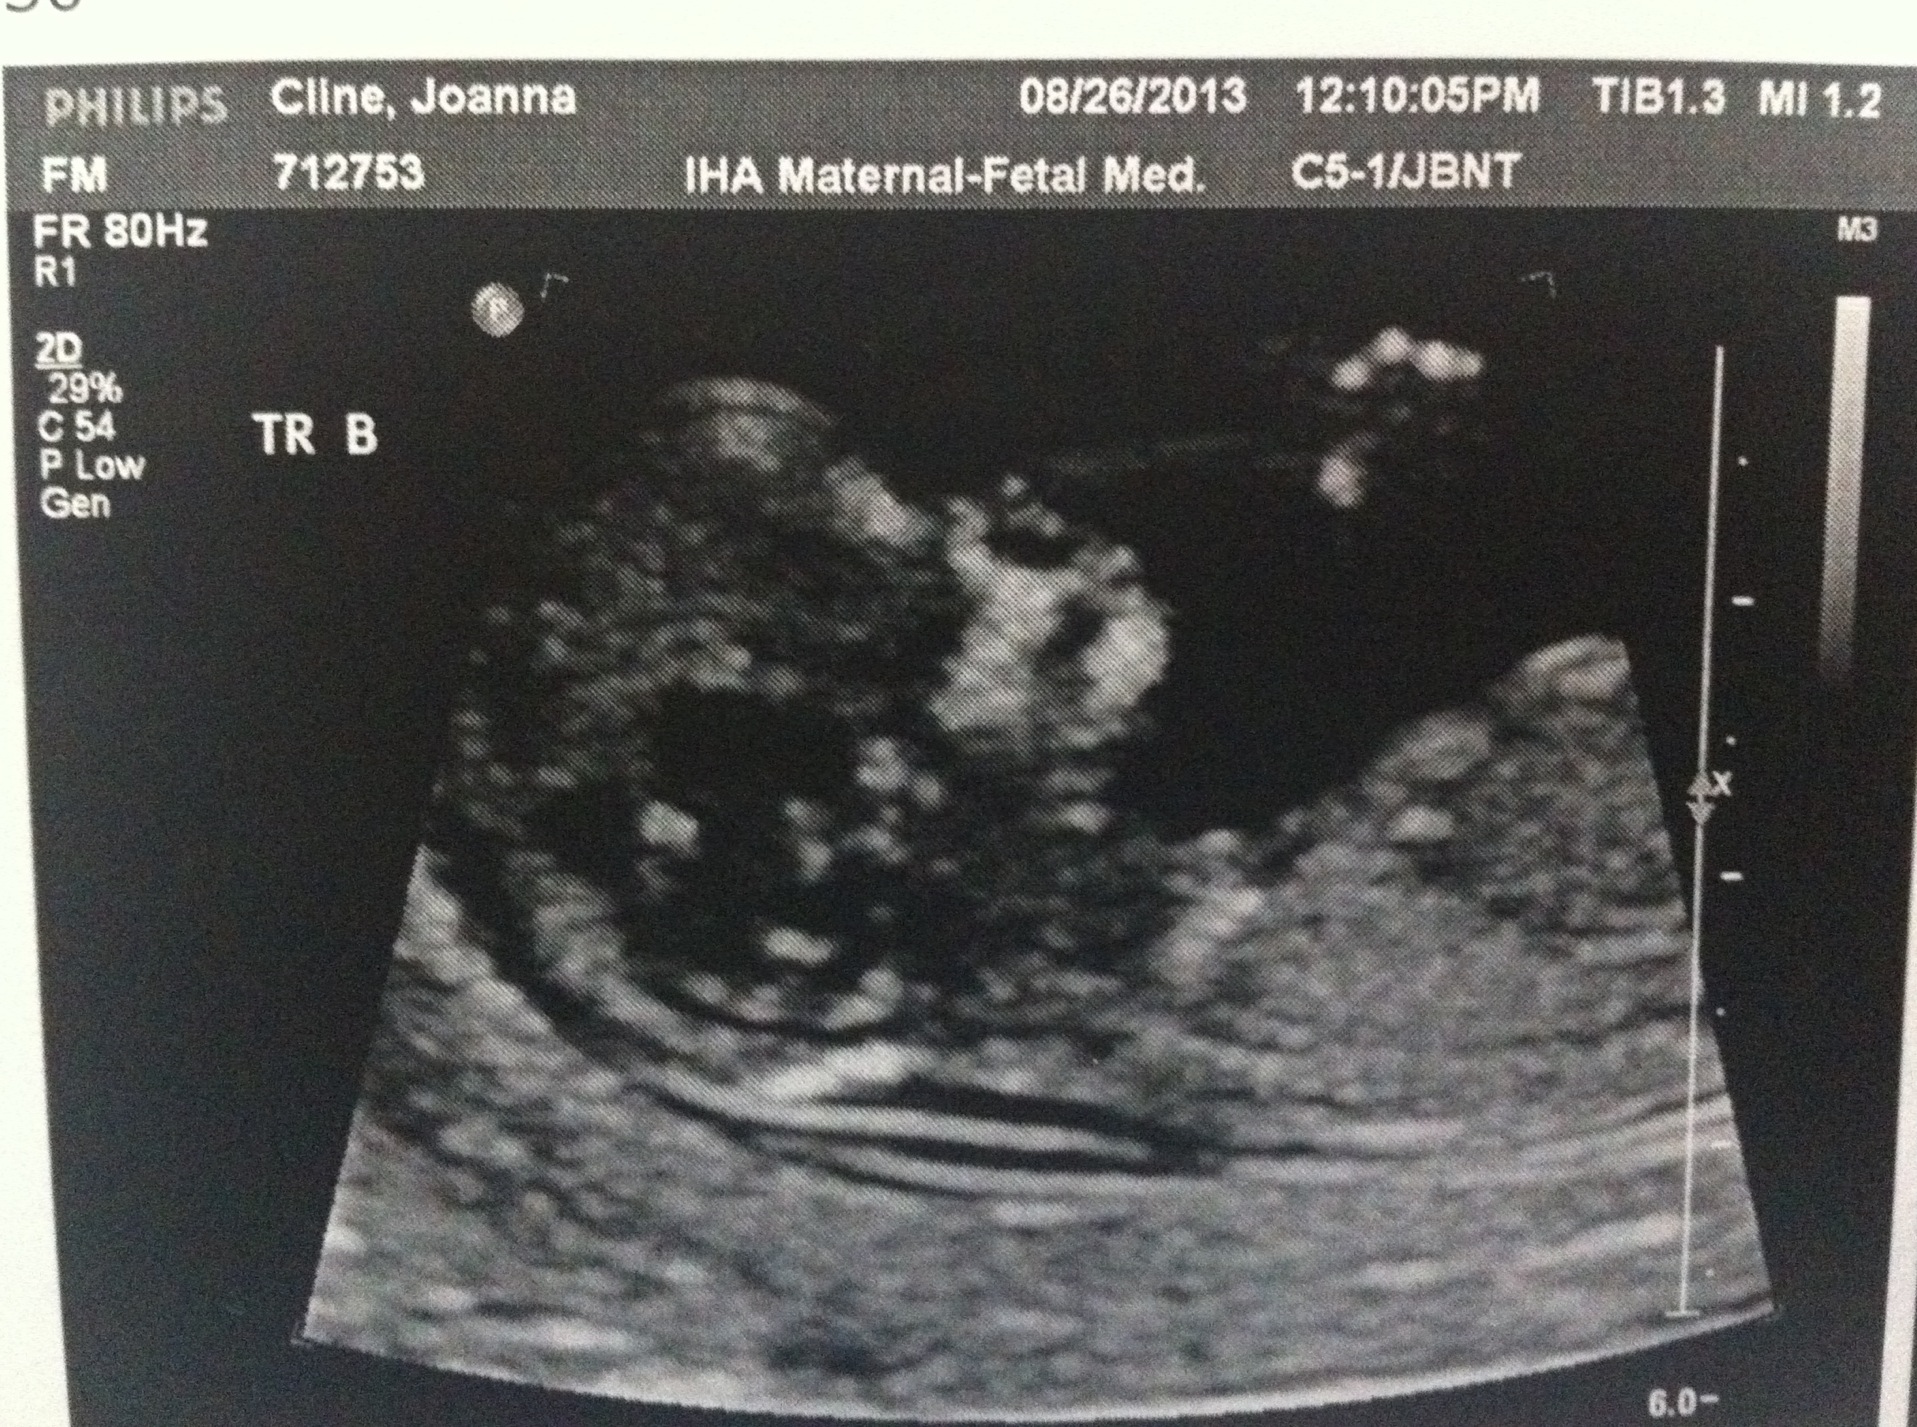

Hello! Today was the all important 12 week ultrasound and everything was great! The fetuses are all measuring about 2.5 inches and their hearts are beating strong. They also like to wiggle around a lot which created some challenges for the very patient ultrasound tech. (With three fetuses to measure, it took about 90 minutes.)